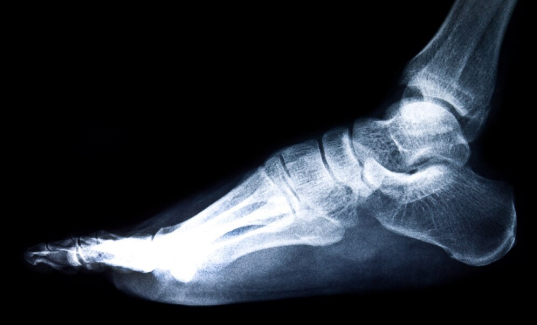

Musculoskeletal (MSK) radiology is a subspecialty of diagnostic radiology that interprets imaging and performs image-guided procedures of the bones, joints, spine and soft tissues for both adults and paediatrics